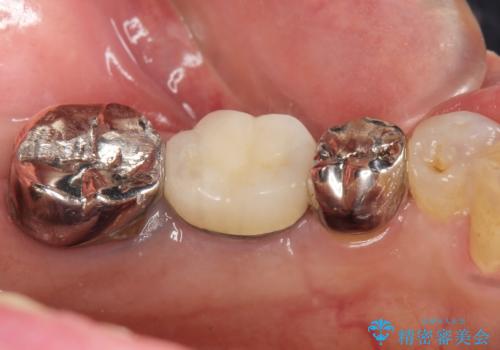

移植後、生着を待って根管治療及び補綴修復を行いました。

機能していない親知らずを用いて咬合を回復することができ、喜んで頂けました。

被せ物の種類:メタルボンドクラウン エコノミー